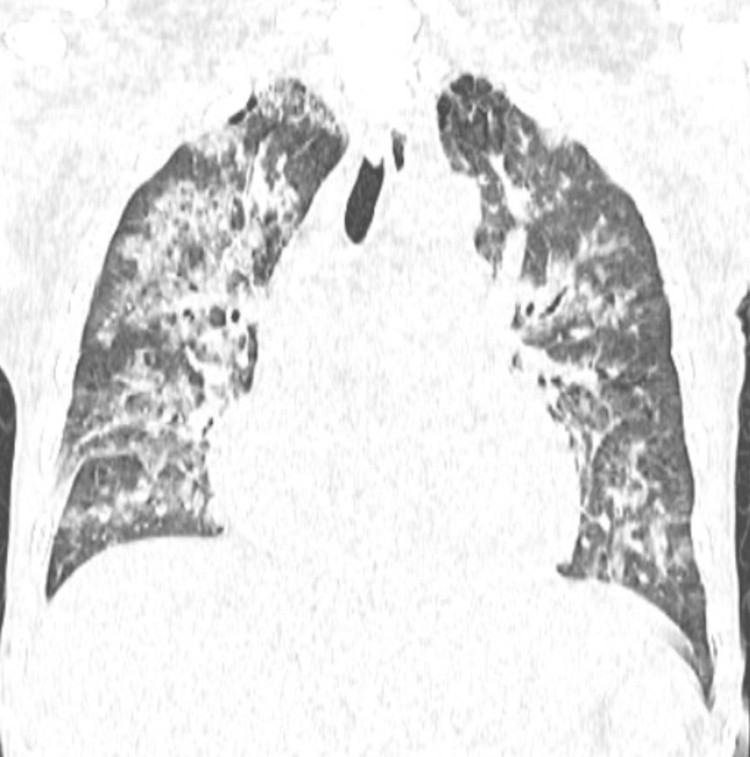

Đến ngày 24/10, trong một lần truyền huyết tương tiếp theo để xử lý tình trạng đông máu, người bệnh xuất hiện khó thở tăng dần chỉ sau khoảng 15-20 phút truyền, SpO₂ từ 97% còn khoảng 88-90%, huyết áp tăng, tĩnh mạch cổ nổi, nghe phổi có ran ẩm hai bên.

Chụp CT scan phổi thấy hình ảnh phù phổi cấp, các xét nghiệm khác phù hợp với chẩn đoán Quá tải tuần hoàn liên quan tới truyền máu (TACO). Kíp trực đã dừng truyền, cho thở oxy, đặt tư thế ngồi và dùng thuốc lợi tiểu, nên người bệnh cải thiện triệu chứng.

phoi.jpg

Phim chụp Xquang phổi của bệnh nhân C.Đ.C (24/10) - Ảnh BVCC